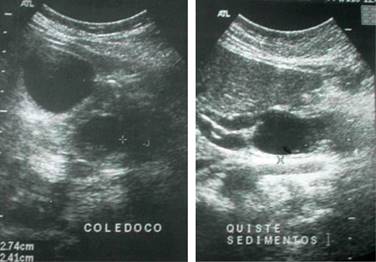

Se realiza otro estudio ultrasonográfico por la consulta externa, encontrándose hígado ecográficamente normal, vesícula biliar anecoica en su interior mide aproximadamente 6.3 x 3.1 cm, pared de 4 mm. Con presencia de quiste de colédoco en región distal con medidas 1.35 x 2.4 x 0.72 cm (Figura 3). Colédoco de calibre normal en su segmento proximal y diámetro de bordes delimitados sin compresión importante de órganos vecinos.

Figura 3: Se realiza otro estudio ultrasonográfico por la consulta externa, encontrándose hígado ecográficamente normal, vesícula biliar anecoica, mide aproximadamente 6.3 x 3.1 cm pared de 4 mm. Con presencia de quiste de colédoco en región distal con medidas 1.35 x 2.4 x 0.72 cm.